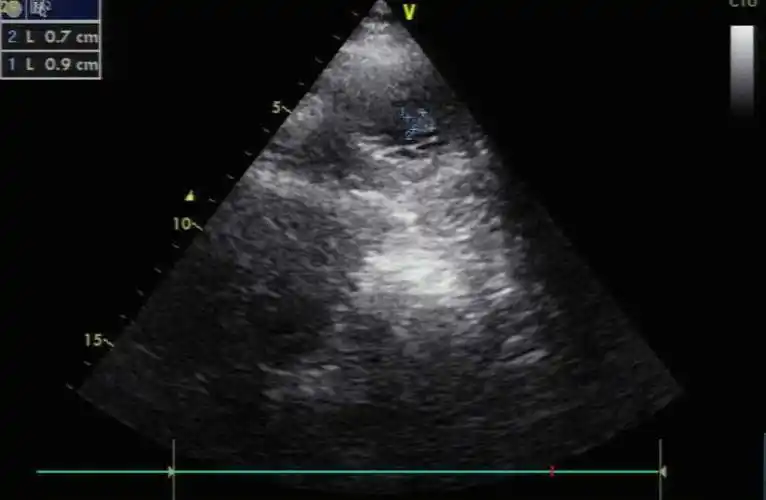

心脏左室短轴切面#医学科普 - 抖音

胸骨旁左心室短轴切面上魏相东读图谈心零基础入门心脏超声

左室短轴切面4声窗7切面搞定急诊超声心动图由浅入深学tte急诊心事

左室短轴切面3d图解心脏解剖与心脏超声切面